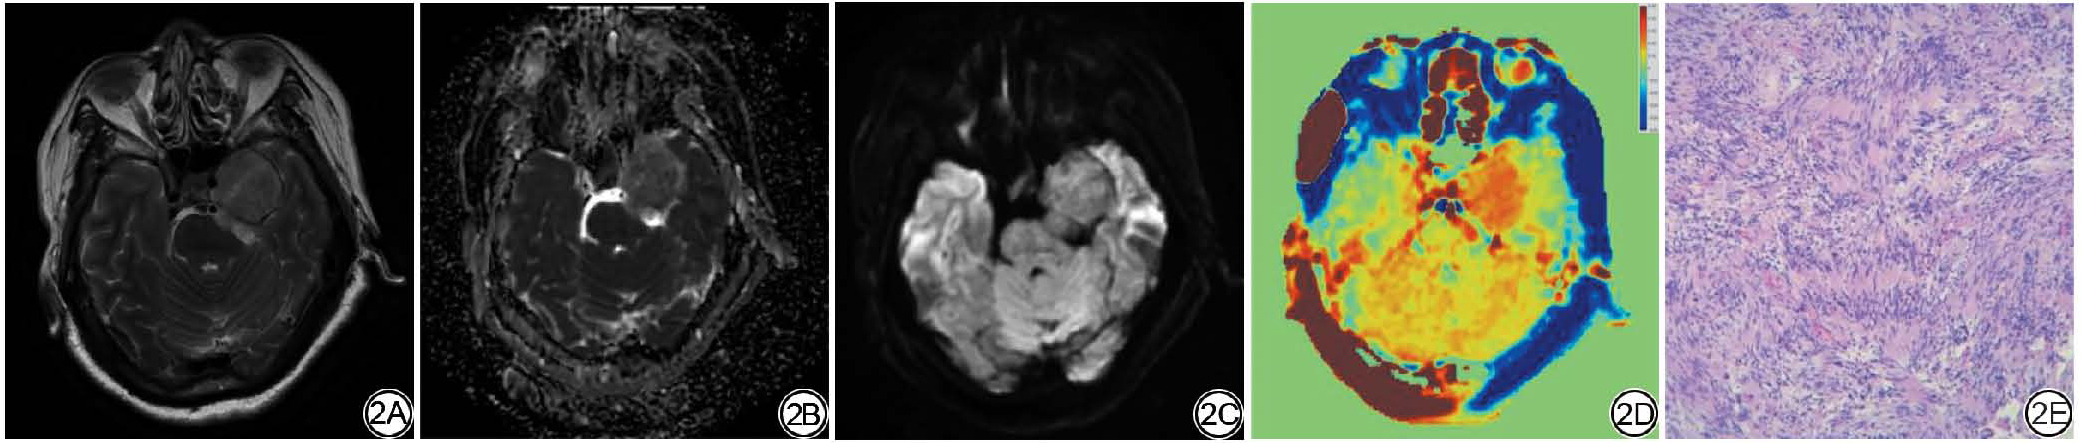

根据本研究设定的纳入及排除标准,71例具有完整病理资料的脑膜瘤患者被纳入,男19例,女52例;年龄为24~79(56.92±10.99)岁。其中,质软组脑膜瘤(图2)33例,非质软组脑膜瘤(图3)38例;两组间在性别、MUSE-DWI信号上差异具有统计学意义(P<0.05),在年龄、肿瘤位置、强化方式、常规MRI信号、有无钙化、水肿、硬膜尾征、WHO分级上差异无统计学意义(均P>0.05)。一般资料见表1

图2  女,57岁,左侧鞍旁脑膜瘤(质软)。2A:术前T2WI;2B:MUSE-DWI衍生成的ADC图呈高信号;2C:MUSE-DWI呈高信号;2D:APT;2E:免疫组化染色病理切片(×200)。T2WI:T2加权成像;MUSE-DWI:多重灵敏度编码扩散加权成像;ADC:表观扩散系数;APT:酰胺质子转移。

Fig. 2  Female, 57 years old, left parasagittal meningioma (soft group). 2A: Preoperative T2WI; 2B: ADC map derived from MUSE-DWI shows high signal intensity; 2C: MUSE-DWI shows high signal intensity; 2D: APT; 2E: Immunohistochemical staining of pathological sections (×200). T2WI: T2-weighted imaging; MUSE-DWI: multiplexed sensitivity encoding diffusion weighted imaging; ADC: apparent diffusion coefficient; APT: amide proton transfer.